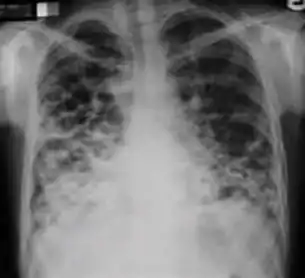

7. Other - Any other finding suggestive of active TB, such as miliary TB. Miliary findings are nodules of millet size (1 to 2 millimeters) distributed throughout the parenchyma.

Chest X-ray of a person with advanced tuberculosis: Infection in both lungs is marked by white arrow-heads, and the formation of a cavity is marked by black arrows.